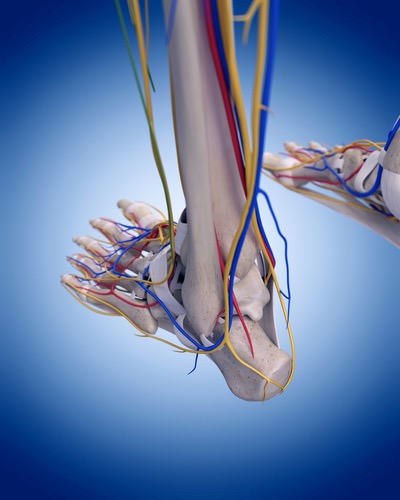

足外側の痛みをスッと取り切る

腓骨神経リリーステクニック

殿部~大腿部の痛みやシビレはとれたけど、膝から遠位部の神経痛がなかなか改善しないといったことは臨床でよく見られるのではないでしょうか?その原因は殿部や大腿部での神経絞扼部のリリースはできているが、この腓骨神経部のリリースができていないからなんです。遠位部の症状は慢性化することでなかなか改善されにくいと思われがちですが、それは間違いです。

Session14

脛骨神経リリーステクニック

脛骨神経は、坐骨神経に由来する総腓骨神経と並ぶやや径の大きな神経で、解剖学的正位で、下腿部においては、膝窩の情報で脛骨に沿って内側を走行します。下肢は坐骨神経の影響が多いと考えられていますが、実はこの脛骨神経由来の症状は臨床上とても多く経験します。特に膝窩部に部分でこの脛骨神経が絞扼されると腰痛を引き起こすことがとても多いです。